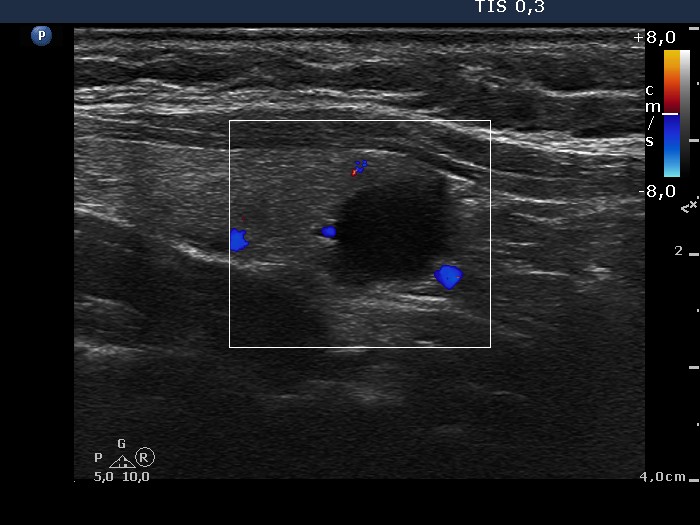

Ultrasonography. The thyroid was minimally hypoechogenic. The left lobe contained a cystic lesion that was completely or almost completely cystic. The lobe had two hypoechogenic nodules next to each other, which presented microcalcifications and irregularly increased intranodular vascularization.

A total thyroidectomy was performed. Histopathology disclosed Hashimoto's thyroiditis. The cystic lesion proved to be a hyperplastic nodule while corresponding to the nodules in the lower part of the left lobe, oxyphilic variant of papillary carcinoma was diagnosed.